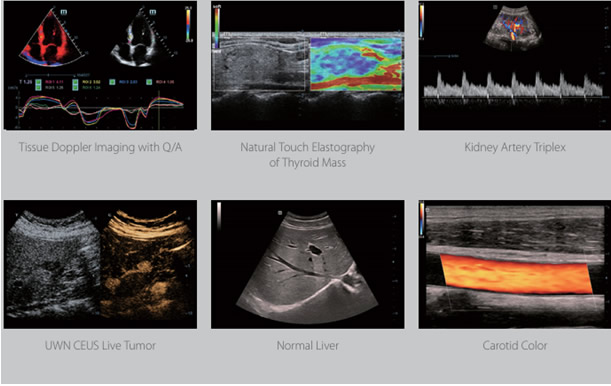

Doppler ultrasound is a special technique based on the principle of the Doppler Effect, which is the change in frequency of sound with movement (imagine of train horn!). This allows us to visualize and assess blood flow in blood vessels and solid tissues.

Ultrasound has uses throughout the body, from looking at the neck vessels for narrowing in those at risk of stroke, evaluating breast masses, looking for gallstones, assessing liver blood flow in cirrhosis, evaluating the uterus and ovaries, finding the source of scrotal pain to assessing tendons and muscles for tears. Most body parts can be evaluated with the exception of the adult brain – the skull is too thick for the sound waves to penetrate – and the lungs- air reflects the sound waves.